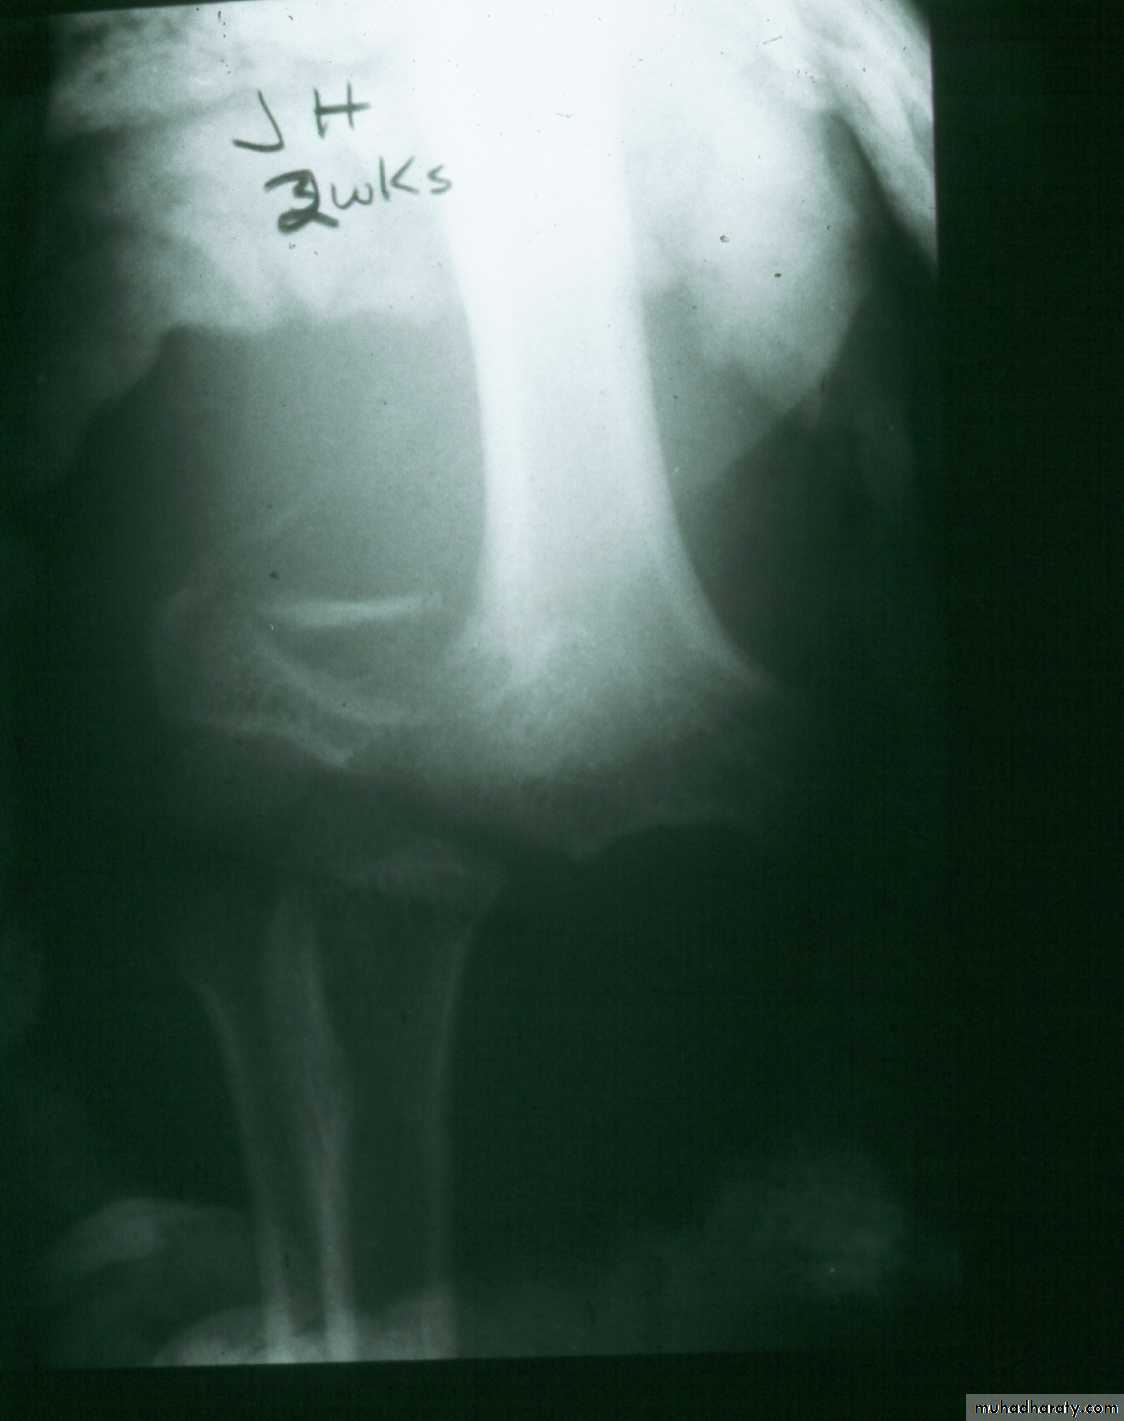

What about late-appearing fractures ?2 wks. post

closed reductionWhat now?

Repeat

closed reduction?

Open reduction?

Periosteal

new bone

Wait. Remodeling can change things.

He had only slight valgus alignment with full elbow motion